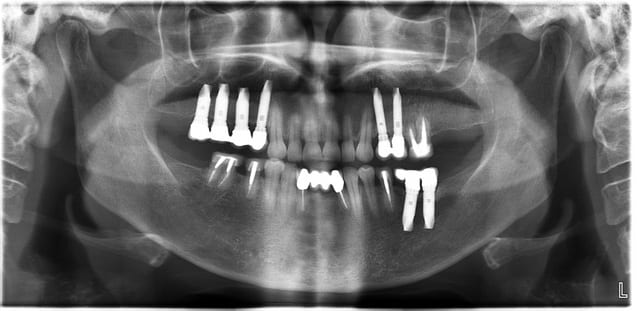

Bourdonnements d'oreilles, céphalées conduisant aux nausées puis vomissements, vertiges invalidants, est restée au lit plusieurs jours de suite, ne supporte plus la lumière et porte des lunettes fumées, fatigue intense. En revanche au niveau des dents aucune douleur n'est évoquée.

Une seconde piste, après la consultation qui a duré 40 minutes elle est repartie totalment soulagée de tous ses maux.

Voyez-vous quelque chose sur cette pano qui pourrait expliquer ceci et puis cela ?

Comment Dieu possible peut-on avoir autant d'os en postérieur (au maxillaire) quand 90% de mes patients ont 4-5 mm grand maximum !!

Sur la pano, il est possible de déceler, du moins le suspecter fortement, ce qui d'un point de vue mécanique est partie prenante et déterminante dans ce qui arrive de fâcheux à la patiente.

Usure des Céram, diminution de la DV?

Taille des implants impressionnante ! Elle risque pas de les perdre...Généralement, migraines,etc =bruxisme . . . Gouttière , problème de dv . . .

la 13 parait bien longue par rapport aux autres ? y'a béance antérieure? égression et prématurité? déséquilibre occlusal? compression articulaire?

= o =... Et 12 ans en arriére il s'est passé quoi ?

usure des 2 centrales sup, non?

Syndrome d'Eagle / ou du processsus styloïde long.

égression 17 ?

peut être une interférence 17 lors des latéralités?

par contre je vois pas pourquoi ça lui fait un problème après 12 ans par contre

(perte 47 récente?)